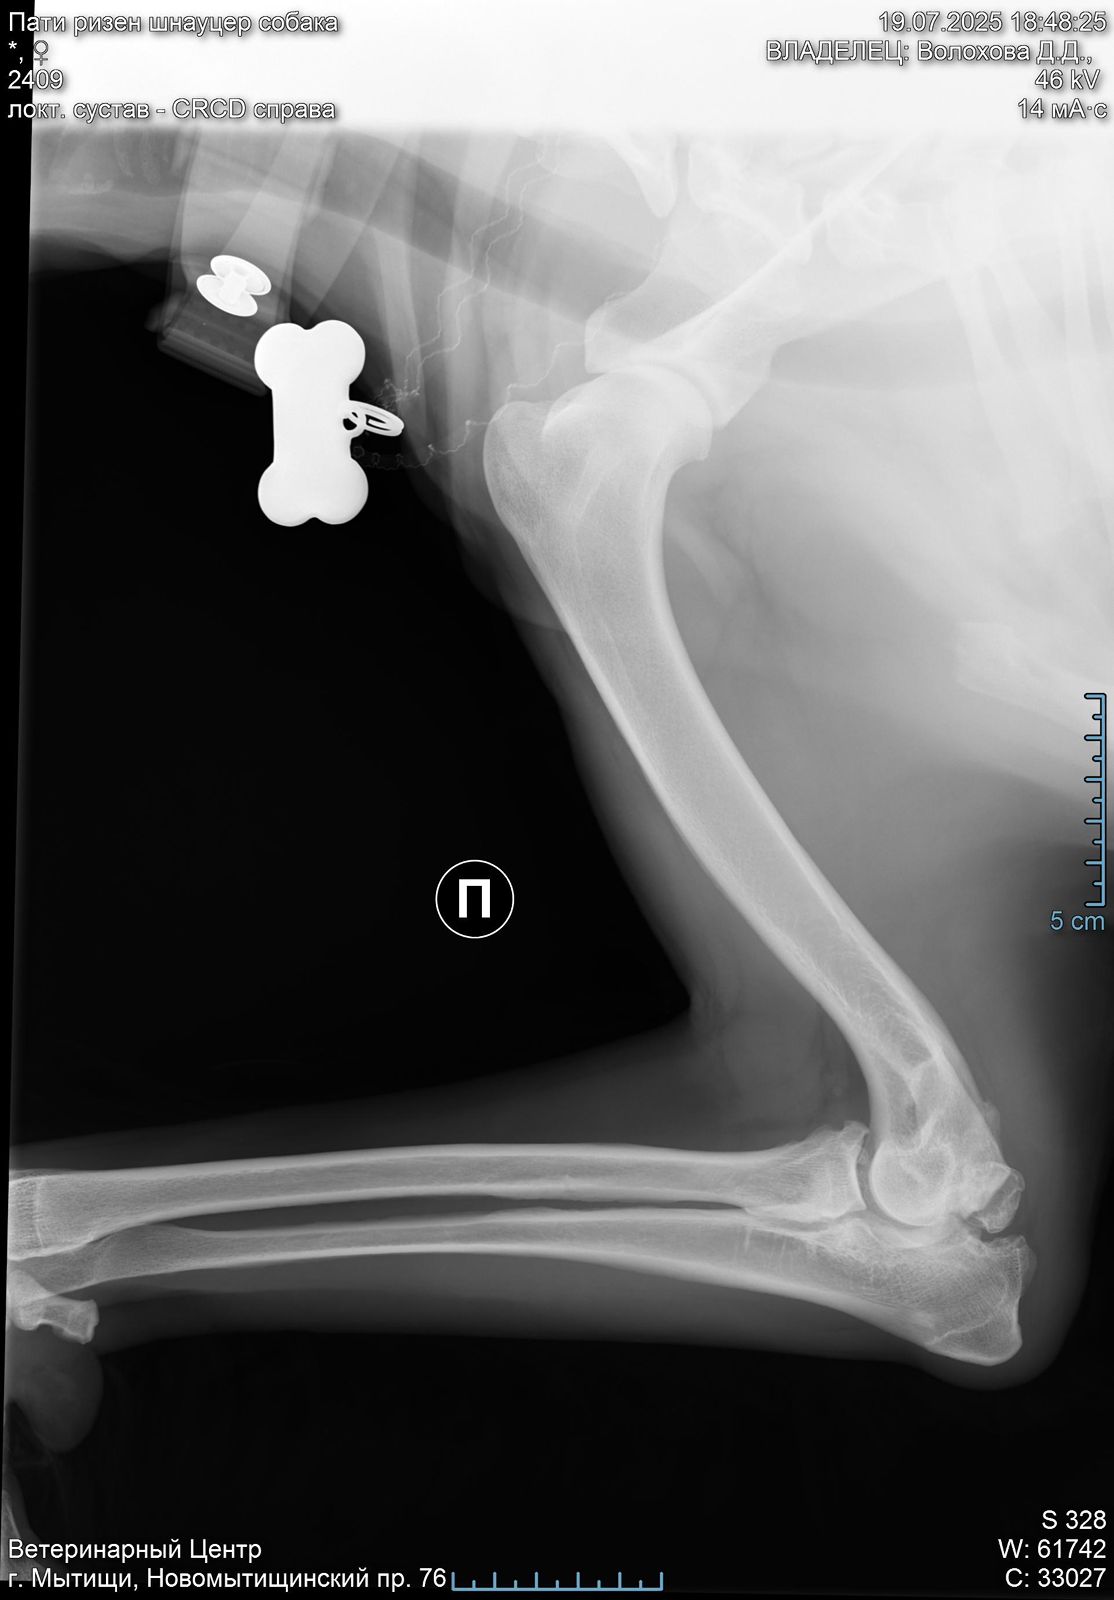

В правом локтевом суставе у Пати болтается 2 осколка кости( от мыщелков).

Их надо убирать.

Проблема не приобретенная у нас, а врожденная или травма в прошлой жизни.

Операция сложная, и делается 2 способами: на открытом суставе или через артроскоп ( если осколки меньше 1 см).

Поэтому вначале требуется КТ, чтоб понимать, какой метод в нашем случае актуален.

Есть шансы поиметь осложнения при обоих. У каждого есть плюсы и минусы.

Но пока есть шанс убрать осколки и жить вполне обычной жизнью ( не спортивной, но и не инвалид).

Артроз сустава никуда не исчезнет, но если повезет, и сильно прогрессировать не будет.

При таком поражении сустава удивительно, что нет выраженной хромоты.

Левый локтевой пока под вопросом, есть там проблемы или нет. КТ покажет.